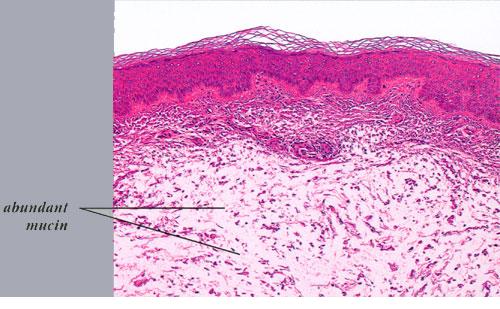

The epidermis and papillary dermis are usually normal. Mucin in large amounts is present in the dermis,

particularly in the upper half . As a result, the dermis is greatly thickened. The mucin occurs not only as individual threads and granules but also as extensive deposits resulting in the splitting up of collagen bundles into fibers and wide separation of the fibers. As a result of shrinkage of the mucin during the process of fixation and dehydration, there are empty spaces within the mucin deposits. The number of fibroblasts is not increased as a rule, but in areas where there is much mucin, some fibroblasts have a stellate shape and are then referred to as mucoblasts . A perivascular infiltrate of lymphocytes may be seen in some cases, and mast cells are moderately increased in number .